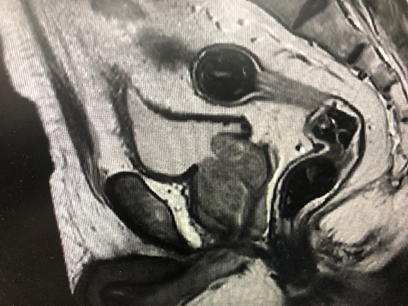

病例一,70岁男性,发现前列腺结节3个月,tPSA 4.66ng/ml,fPSA 0.520 ng/ml,盆腔mri示前列腺结节,Ca?双侧腹股沟多发稍大淋巴结。前列腺穿刺活检示前列腺腺泡腺癌,4针阳性,Gleason评分4+4=8分,行机器人辅助腹腔镜前列腺癌根治术+盆腔淋巴结清扫术,术者:王国良教授。